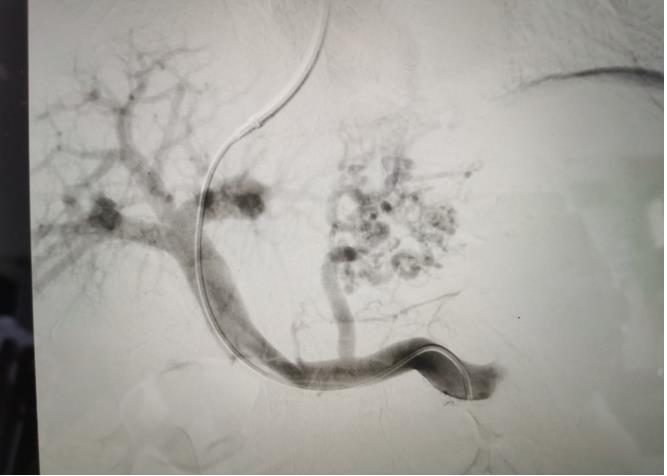

經(jīng)過我院血管介入科醫(yī)療團隊的精心準備,患者在數(shù)字減影血管造影機(DSA)導(dǎo)引下,順利經(jīng)頸靜脈入路進入下腔靜脈并成功穿刺了門靜脈右支主干,術(shù)中栓塞了曲張的胃冠狀靜脈-食管靜脈叢將支架植入肝實質(zhì)內(nèi),支架兩端分別置于門靜脈和肝靜脈內(nèi),術(shù)程歷時2小時,術(shù)中患者時刻保持清醒,手術(shù)切口僅5毫米,術(shù)后第2天恢復(fù)飲食,腹脹、腹水癥狀明顯好轉(zhuǎn),未出現(xiàn)嘔血、黑便及肝性腦病等并發(fā)癥,術(shù)后第3天康復(fù)出院。